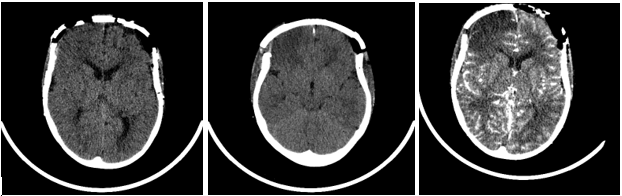

A pre-assessment CT brain for preparation of cranial vault remodeling showed scaphocephaly with sagittal synostosis, premature almost complete fusion of lambdoid suture, and delayed closure of anterior fontanelle. Diffuse thickening of the skull base and calvarium, under pneumatization of the mastoid air cells and paranasal sinuses and bony facial features consistent with the history of osteopathia striata with cranial sclerosis, there is also associated cleft palate, bony defect commencing 5 mm posterior to the incisive foramen (Figure 1A).

Figure 1: A) Preoperative CT brain showing diffuse thickening of the skull base and calvarium. B) Preoperative CT brain showing CT 3D Skull Facial Bones-lateral view. C) Postoperative 3D CT skull showing good approximation.

Day 1 postoperatively she developed left-sided focal seizures (left arm jerking, left facial twitching) 8 seizures were recorded in total lasting approximately between 30s-35mins. The first seizure initially responded to buccal Midazolam, but the seizures were fully abated by Phenytoin and Phenobarbitone. On examination following the seizures, she was noted to have left-sided weakness (left hemiparesis). A subsequent CT Brain revealed acute right frontal and medial right parietal infarcts (Figures 2A & 2B). An MRI brain showed extensive bilateral areas of acute infarct distribution suggestive of watershed infarcts worse on the right side and absence of signal flow within the supraclinoid segment of both internal carotid arteries (ICA). CTA showed absence of flow with the supraclinoid segments of both ICA, in keeping with occlusion and evolution of bilateral infarcts right greater than left (Figure 2C). She was then commenced on Aspirin. IR with general anaesthesia (GA) revealed bilateral supraclinoid ICA occlusion, consistent with moyamoya syndrome (bilateral occlusive cerebrovascular disease) (Figures 3A & 3B). Following the review of imaging by a multidisciplinary team, it was agreed that she was not fit for any pial synangiosis surgery or burr hole surgery in relation to the moyamoya disease as she was at very high risk of further strokes and surgery should be avoided wherever possible as the risk of general anaesthesia would also be considerable for her.

Figure 2: A & B) CT brain shows CT brain right frontal and medial right parietal infarcts. C) CTA shows-Interval expected evolution of the bilateral infarcts (R>L).